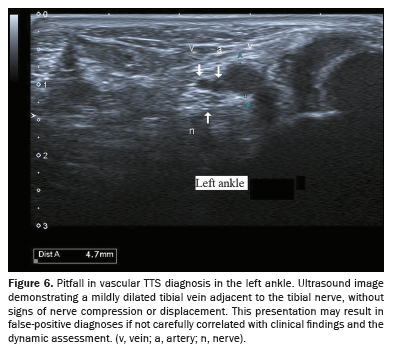

Pitfalls and false positives are important considerations in the ultrasonographic diagnosis of vascular TTS. Dilated veins within the tarsal tunnel are not uncommon and may be seen in asymptomatic patients, particularly those with chronic venous insufficiency (Figure 6). For example, mild varicose plantar veins that do not directly impinge on the tibial nerve may appear significant on imaging but do not correlate with symptoms. Similarly, positional changes during scanning can transiently enlarge veins without true nerve compression. Inexperienced operators may also misinterpret normal vascular variants, such as prominent medial plantar veins, as pathological findings. Therefore, careful clinical correlation, dynamic scanning in the supine and standing positions, and recognition of nerve contact or displacement are essential to avoid overdiagnosis and unnecessary interventions.